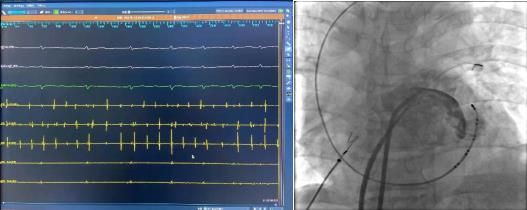

术前腔内电图可见毫无规律的房颤波,接着穿刺房间隔建立左房通路。完成肺静脉隔离及顶部线消融后房颤转复为规律的心房扑动。

激动标测提示二尖瓣峡部依赖性房扑,而在消融过程中发现患者肌袖比较发达,进行二尖瓣峡部线性消融后不能终止房扑,结合患者情况决定进行Marshall静脉酒精消融。

冠状窦造影定位Marshall静脉,应用OTW球囊进行酒精消融